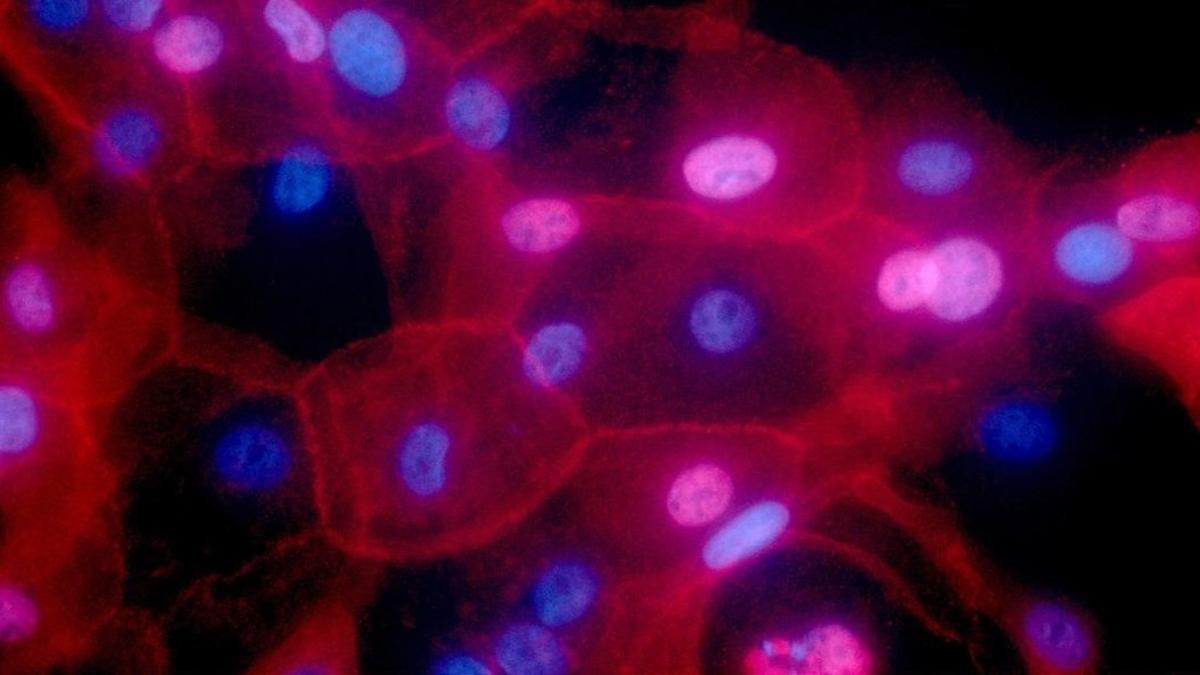

zentauroepp37788452 this undated fluorescence colored microscope image made avai170323210312 / AP

Cerca de dos tercios de los cánceres son causados por errores casuales en el ADN que ocurren cuando las células normales hacen copias de sí mismas, un hallazgo que ayuda a explicar por qué las personas sanas que hacen todo lo posible para evitar el cáncer siguen siendo afectadas por la enfermedad, según el estudio de unos investigadores estadounidenses publicado este jueves en la revista 'Science'.